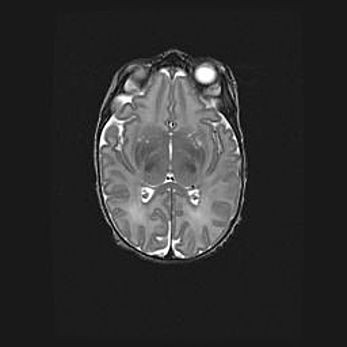

Множественные кисты обоих полушарий головного мозга, наибольшая из них в правой затылочной области. Ассиметричная атрофическая гидроцефалия.

Возраст: 7 месяцев

Вес: 5660 г

Пол: мужской

Окружность головы: 41,5 см

Срок гестации: 28-29 недель

Кисты головного мозга развиваются в результате многоочаговых некрозов вещества мозга и возникают вследствие перенесенной перинатальной инфекции, менингитов, энцефалитов, асфиксии, родовой травмы, расстройств мозгового кровообращения различного генеза. Образованию кист в веществе головного мозга плодов и новорожденных способствуют такие факторы, как высокое содержание в нем воды, недостаточная (или отсутствие) миелинизация и слабая астроглиальная реакция на повреждение.

Кисты могут сочетаться с гидроцефалией и другими поражениями головного мозга.